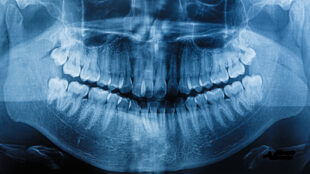

Snarkning skadar gomseglet

Snarkare får med tiden vävnadsskador i gomseglet som kan förklara varför så många drabbas av sömnapné, visar...